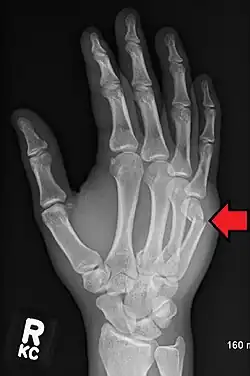

Boxer's fracture of the 5th metacarpal head from punching a wall | |

A boxer's fracture is the break of the fifth metacarpal bone of the hand near the knuckle.[4] Occasionally, it is used to refer to fractures of the fourth metacarpal as well.[1] Symptoms include pain and a depressed knuckle.[2]

Classically, it occurs after a person hits an object with a closed fist.[3] The knuckle is then bent towards the palm of the hand.[3] Diagnosis is generally suspected based on symptoms and confirmed with X-rays.[3]

Diagnosis by a doctor's examination is the most common, often confirmed by x-rays. X-ray is used to display the fracture and the angulations of the fracture. A CT scan may be done in very rare cases to provide a more detailed picture.